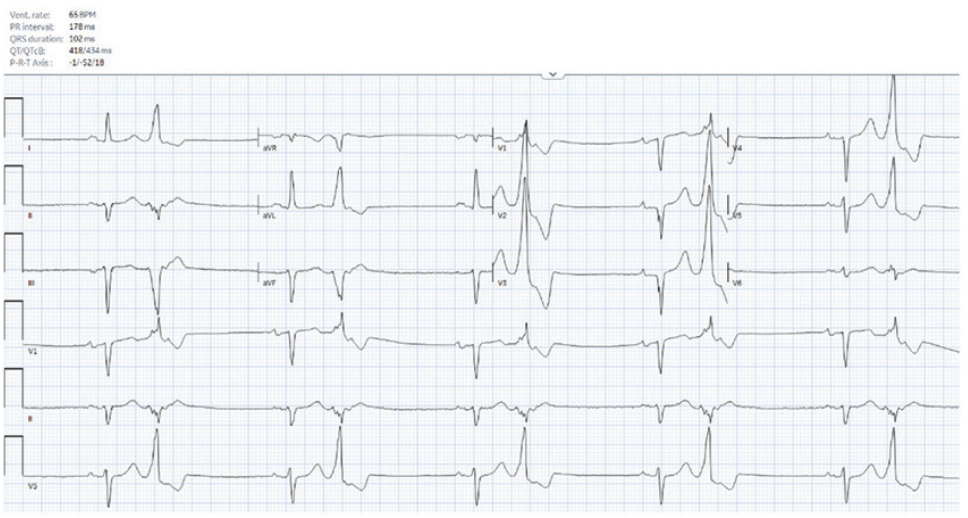

A 54-year-old man with coronary artery disease status post stenting of the right coronary artery and systemic sclerosis with subendocardial fibrosis of the mid and basal inferoseptum and inferior wall on cardiac magnetic resonance imaging was referred for frequent, highly symptomatic, unifocal, premature ventricular contractions (PVCs) with a right bundle superior axis morphology. He was in ventricular bigeminy when seen in clinic (Figure 1) and had a PVC burden of 27% on a recent Holter. He underwent an attempted ablation procedure a few months earlier, during which the PVCs were mapped to the posterior papillary muscle and inferior left ventricular (LV) base. Activation times were reported to range from 0 to -20 milliseconds pre-QS; however, ablation was unsuccessful. What factors contributed to the unsuccessful ablation, and what considerations should be made for the redo procedure?